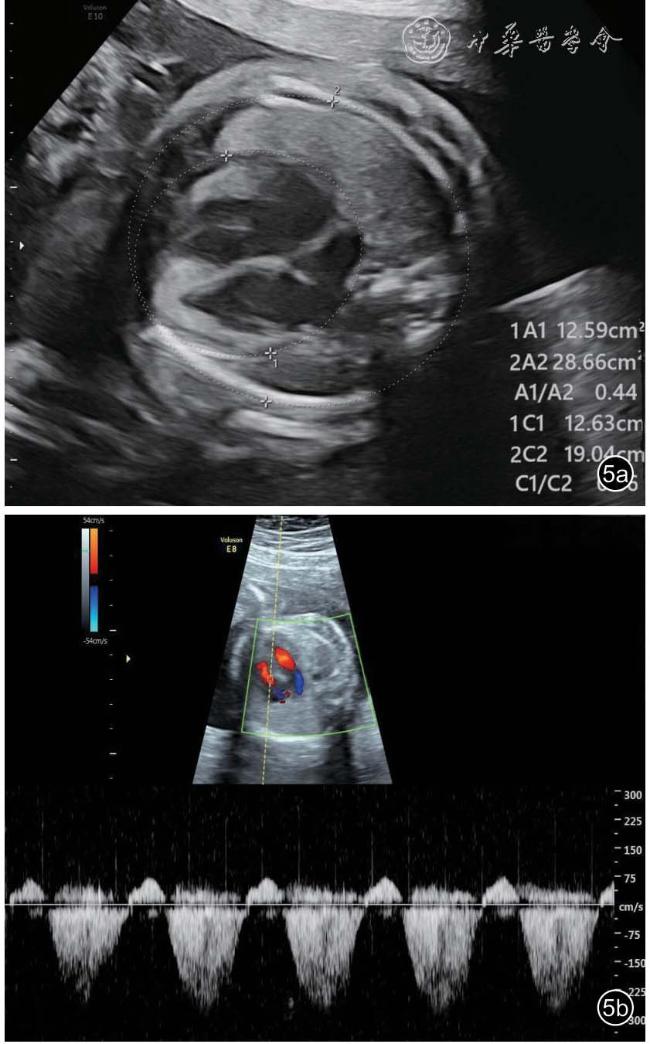

图5 双胎贫血-红细胞增多序列征胎儿孕23+5 周产前超声图像。图a:可见供血儿心胸比增大(约为0.44);图b:彩色多普勒可见二尖瓣、三尖瓣轻度反流束,连续多普勒测及反流速度约为2.7 m/s